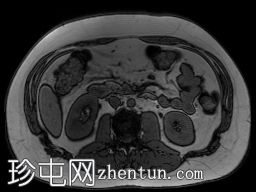

冠状位

T2加权像

T1低信号,T2低信号为主的脾脏肿块,内部可见T2高信号分隔,呈进行性强化。肿块中央可见星状瘢痕。

脾脏硬化性血管瘤样结节性转化(SANT),9.8 cm肿块

顾名思义,脾脏硬化性血管瘤样结节性转化(SANT)是一种纤维性血管病变。本病例展示了SANT的一些典型影像学特征,包括边界清晰的病灶,中央可见瘢痕,以及呈放射状进行性强化。这些特征使得术前MRI诊断较为明确。尽管SANT是一种良性病变,但大多数患者仍需行脾切除术以明确病理诊断。